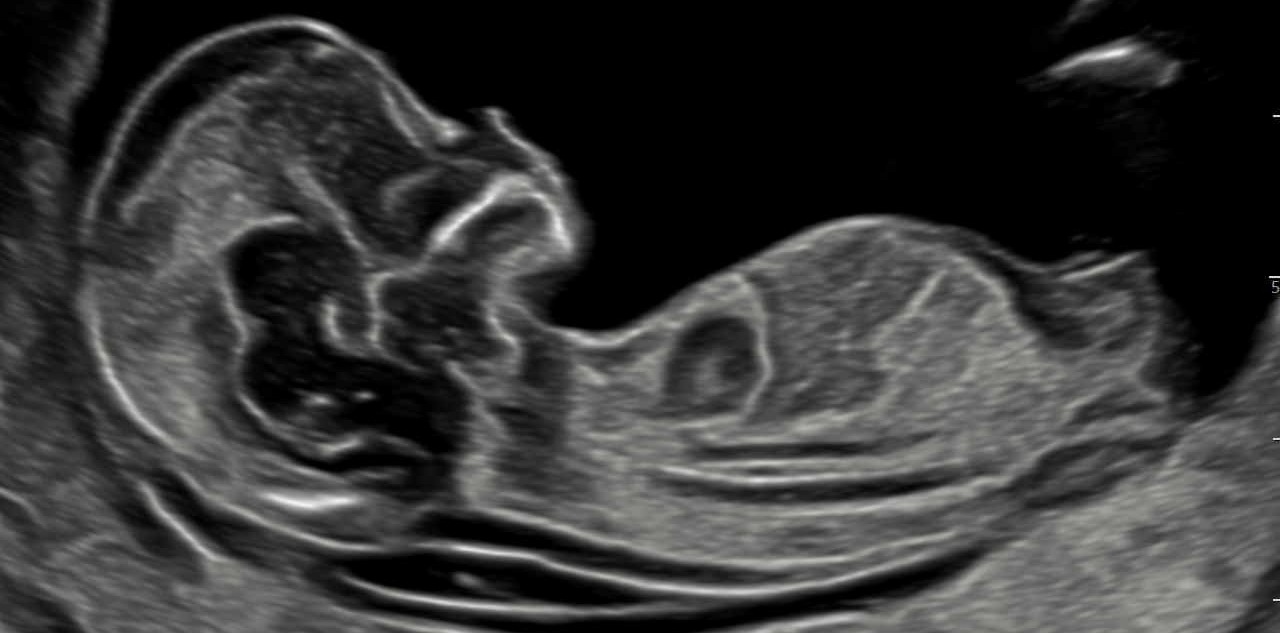

„Feindiagnostik“: 20-24 SSW

Wir schauen Ihr Kind im Ultraschall detailliert von Kopf bis Fuß an. Mit Fortschreiten der Schwangerschaft liegt der Fokus hier besonders auf der Entwicklung von Herz und Kopf Ihres Kindes. So können wir Besonderheiten frühzeitig erkennen, die Schwangerschaft optimal begleiten und die Geburt bestmöglich vorbereiten. In manchen Fällen ist eine Behandlung bereits während der Schwangerschaft möglich.

Je nach Fragestellung kann diese Untersuchung auch zu einem deutlich früheren oder späteren Zeitounkt sinnvoll sein.